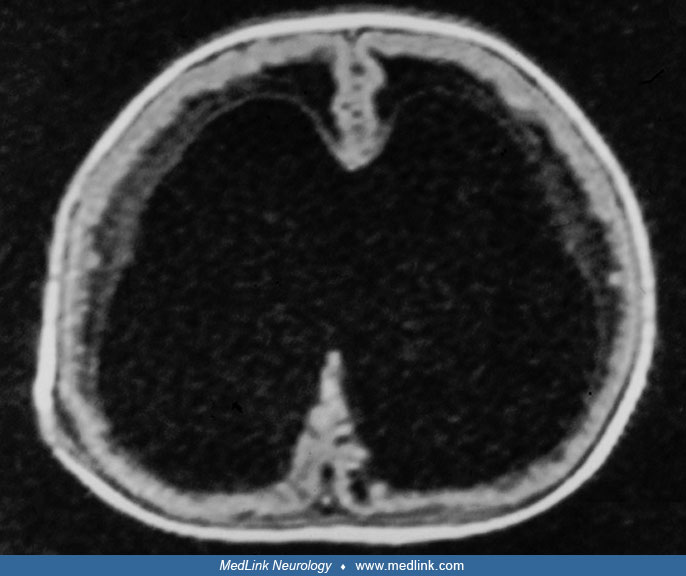

From www.medlink.com

wwpb3e MedLink Neurology Walkers Syndrome The condition, which occurs in one in every 25,000 to 35,000 live births each year, causes different parts of the cerebellum to develop abnormally. It’s a congenital brain malformation that causes. This can cause issues with. The symptoms of dandy walker syndrome typically include developmental delay, low tone (hypotonia) or later high tone (spasticity),. Walkers Syndrome.